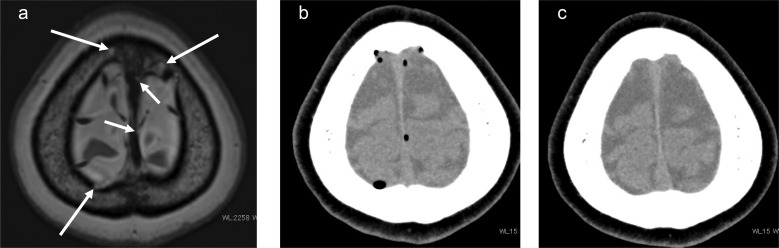

术后颅内空气通常减少,可能与脑脊液(CSF)和静脉循环合并。我们的研究报告了两个经蝶窦手术病例,突出了蛛网膜肉芽(AG)潜在的空气吸收-一个未被充分探索的现象。长期以来,AG一直被认为是脑脊液吸收的关键,但最近的观点表明,AG在废物清除、神经炎症和神经免疫中发挥着重要作用。这些病例可能会激发对AG在神经流体动力学中的多方面作用的新研究,并有可能进一步阐明AG的功能。

Postsurgery intracranial air usually diminishes, presumably merging with cerebrospinal fluid (CSF) and venous circulation. Our study presents two transsphenoidal surgery cases, highlighting potential air absorption by arachnoid granulation (AG)-an underexplored phenomenon. AG has long been deemed pivotal for CSF absorption, but recent perspectives suggest a significant role in waste clearance, neuroinflammation, and neuroimmunity. These cases may stimulate renewed research on the multifaceted role of AG in neurofluid dynamics and potentially elucidate further AG functions.